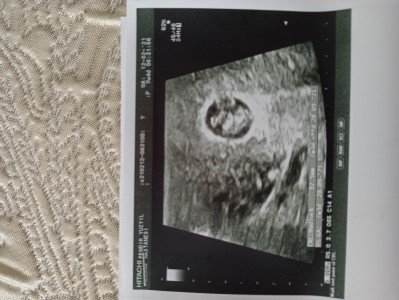

7hafta 4gunluk hamileyim Dr bebeğin keseyi biraz tam doldurduğunu bunun sıkıntı olabilecegini takip etmek gerektiğini söyledi böyle bir durum yaşayan olmuş muydu kalbini duyduk bu arada

hayrli olsun.bi bilgim yok ne yazikki.ama resimdede goruluyor buyuk gibi geldi genelde kese daha buyuk bebek kucuk olur sizde baya tutmus keseyi.

bence yeri dar oldugu icin kalb durmasi sikistrmasi gibi sorunlara yol.acar diye dusunuyorum.ama oyle bisey olmaz insAllah drun dediyini yapin siz sik sik muayine olun .sagsalim kucaginiza alirsiniz insAllah